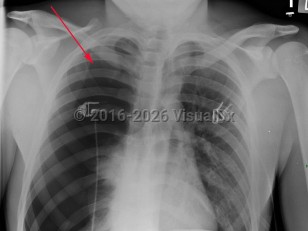

Spontaneous pneumothorax

Spontaneous pneumothorax (SP) is caused by the introduction of air between the visceral and parietal pleura, typically as the result of trauma. SP can be classified as either primary or secondary. The presence or absence of lung disease distinguishes the primary form from the secondary form. Primary SP (PSP) lacks underlying lung disease, whereas secondary SP (SSP) patients have a preexisting condition such as chronic obstructive pulmonary disease  (COPD; a majority of cases), cystic fibrosis, pulmonary infection, interstitial lung disease (especially histiocytosis and sarcoidosis), AIDS, neoplasms, or drug use.

The size of the pneumothorax, rate of development, and underlying clinical status determine the clinical presentation. Those with a mild PSP may not seek care, while those with SSP present acutely. The range of signs and symptoms include acute pleuritic chest pain (localized to the side of the pneumothorax), dyspnea, decreased breath sounds, tachypnea, tachycardia, hyperresonance, unilaterally decreased lung sounds, or acute decompensation.